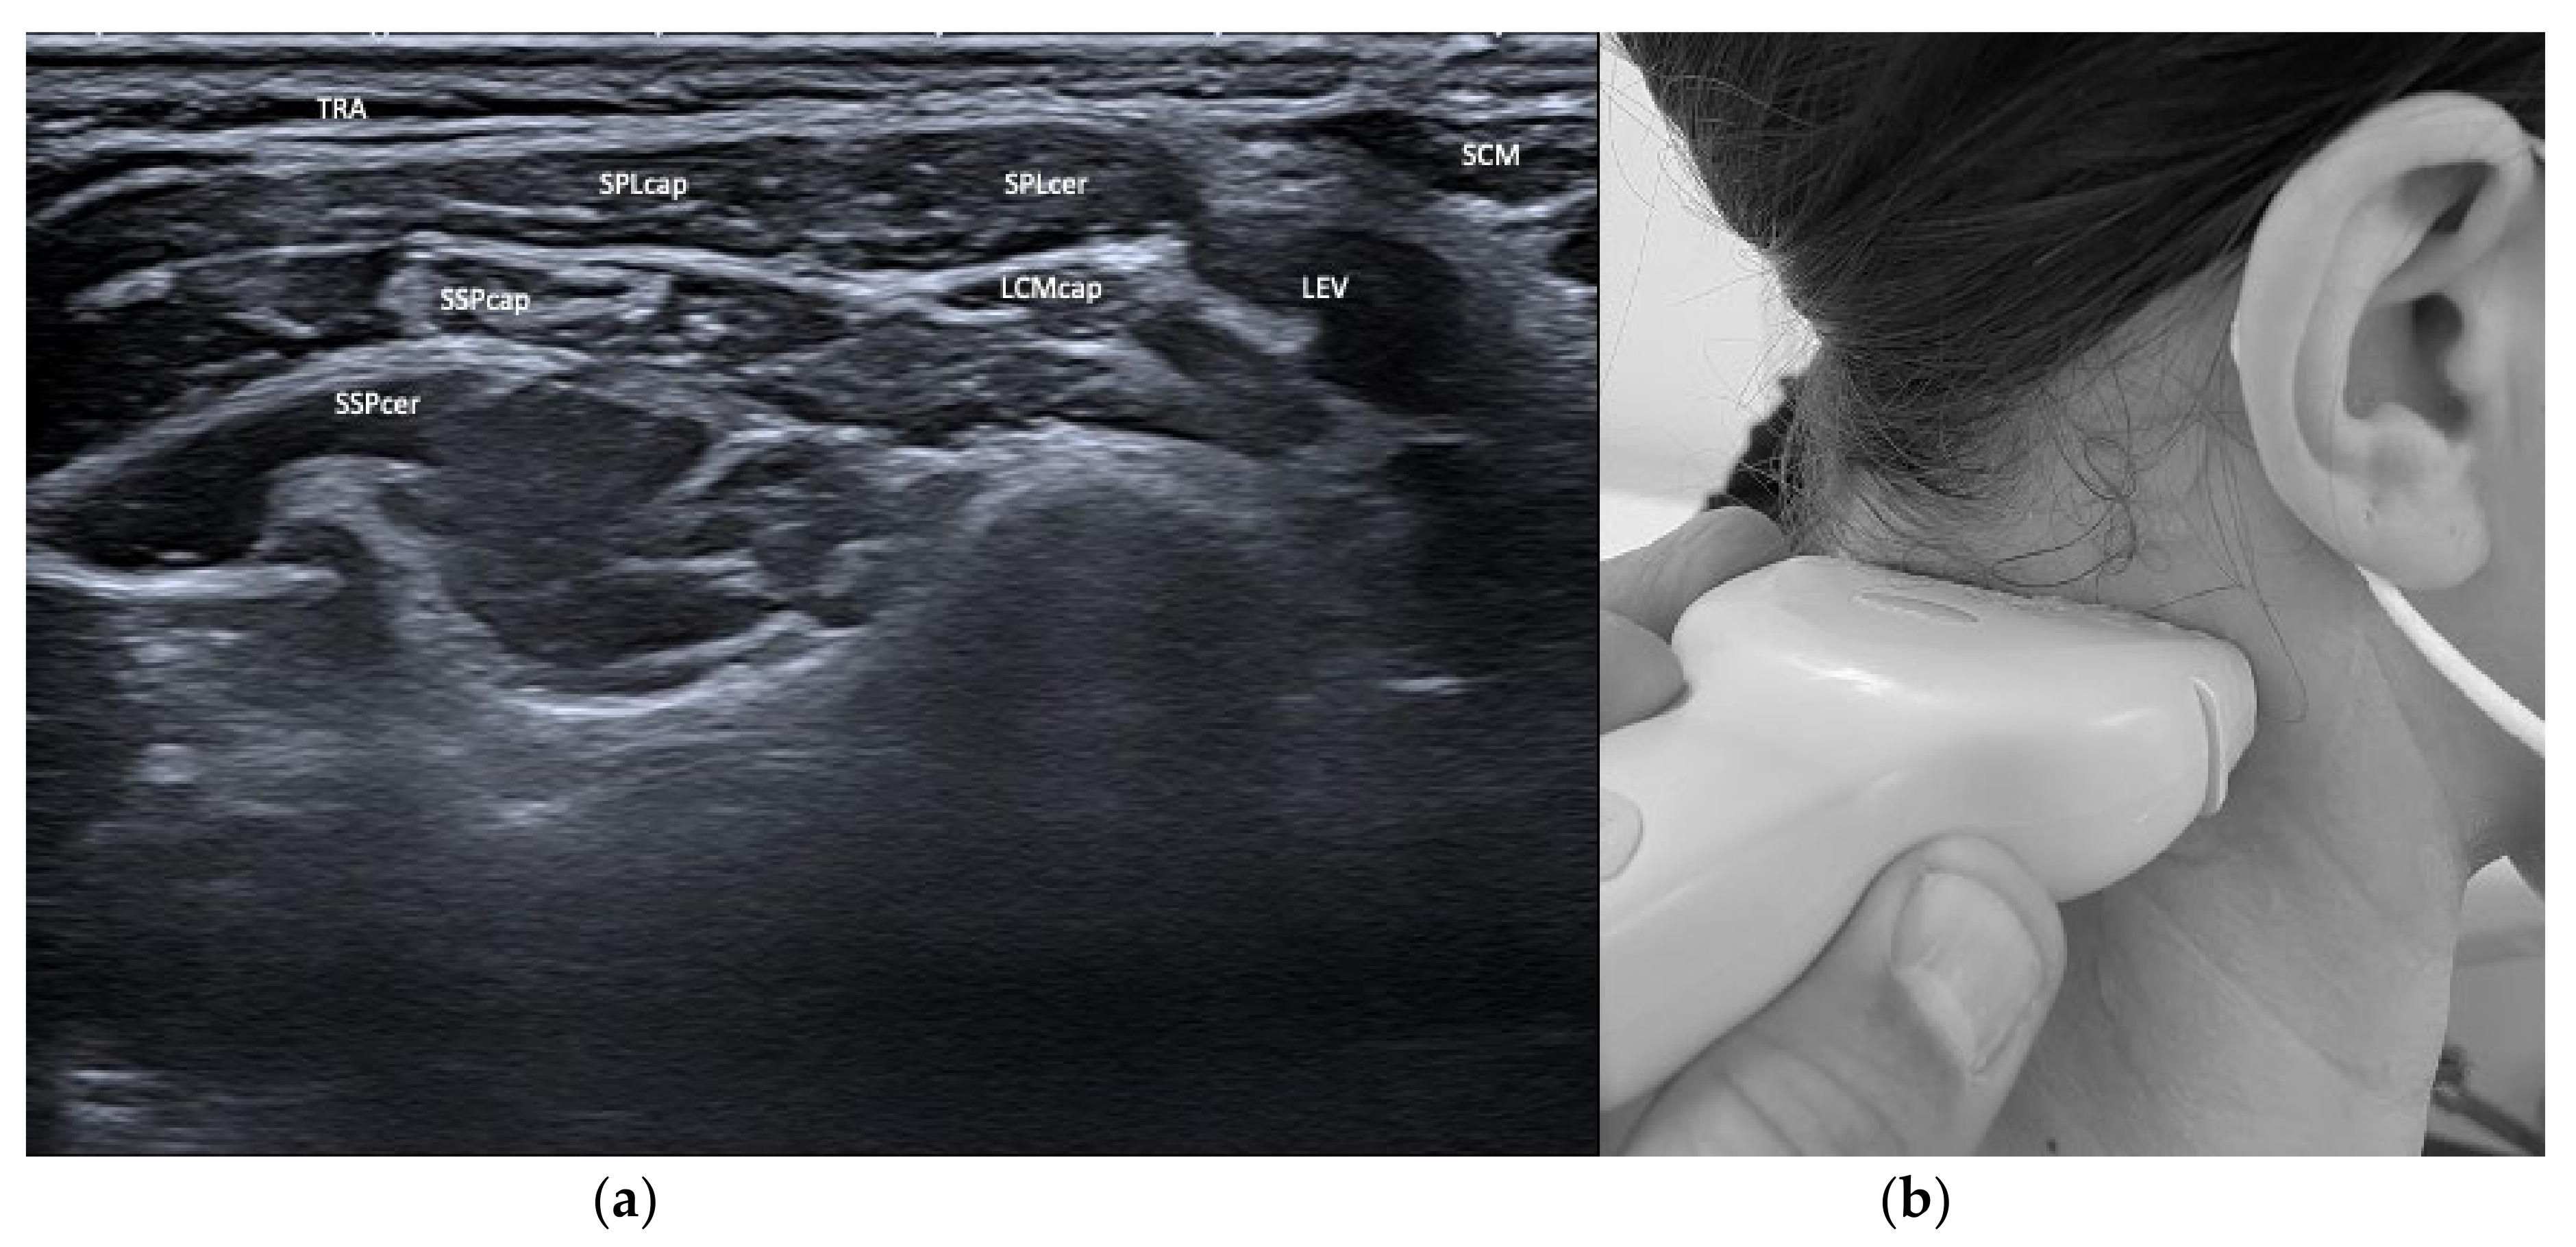

3.1. Layers and Compartments

3.2. Orientation of Layers—Reciprocal Function of Neighboring Structures

| Semispinalis capitis (SSPcap) | Extension of head | + | + | SPLcap, OCI | Strongest extensor muscle of head and neck |

| Semispinalis cervicis (SSPcer) | Extension of neck | + | + | SPLcer, TRA | |

| Splenius capitis (SPLcap) | Ipsiversion of head | ++ | ++ | major occipital nerve, SPLcap/cer, LSMcap, OCI | Prominent reduction in bulk from repeated injections possible |

| Splenius cervicis (SPLcer) | Ipsiversion of neck | +++ | ++ | LEV, TRA, Longissimus cervicis | Relevant for full turn of the neck |

| Longissimus capitis (LCM) | Ipsiversion of head and neck | +++ | ++ | SPLcap, SSPcap | Obligatory USG |

| Trapezius (TRA) | Extension of neck | + | + | LEV, Supraspinatus | |

| Levator scapulae (LEV) | Lift of scapula | + | + | SPLcer, TRA | |